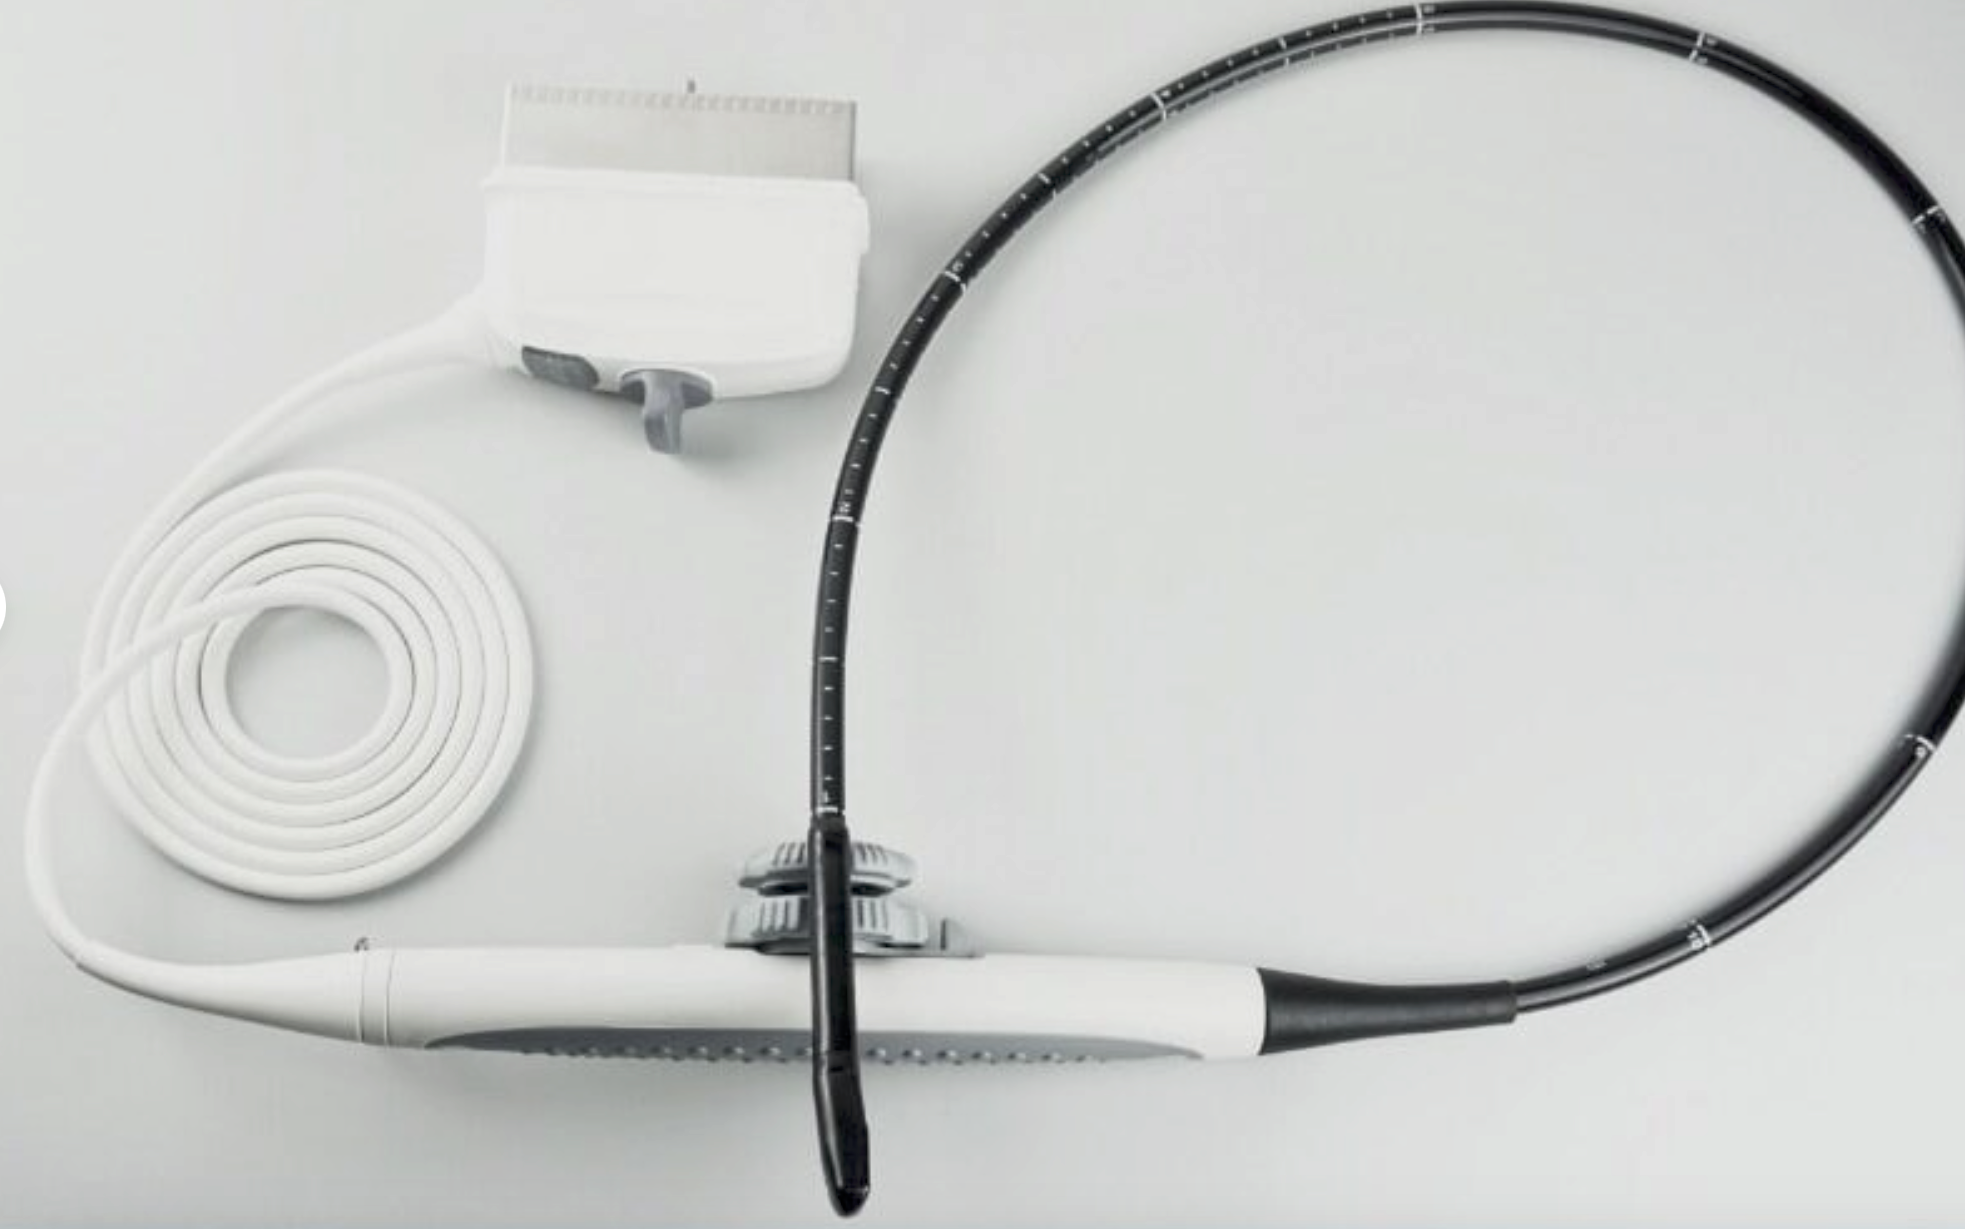

Acquire a trusted healthcare companion with our Philips IU22 3D/4D Ultrasound System, now available for purchase. This pre-owned model, possessing a legacy of reliability, is being offered in an excellent operational condition and comes with a complete set of four probes.

Comprehensive Functionality: Despite showing minimal signs of cosmetic wear, the unit remains fully functional and geared for immediate clinical deployment. All probes have been diligently tested to ensure optimal performance. Extensive care has been taken to maintain the system, reaffirming its condition akin to new.